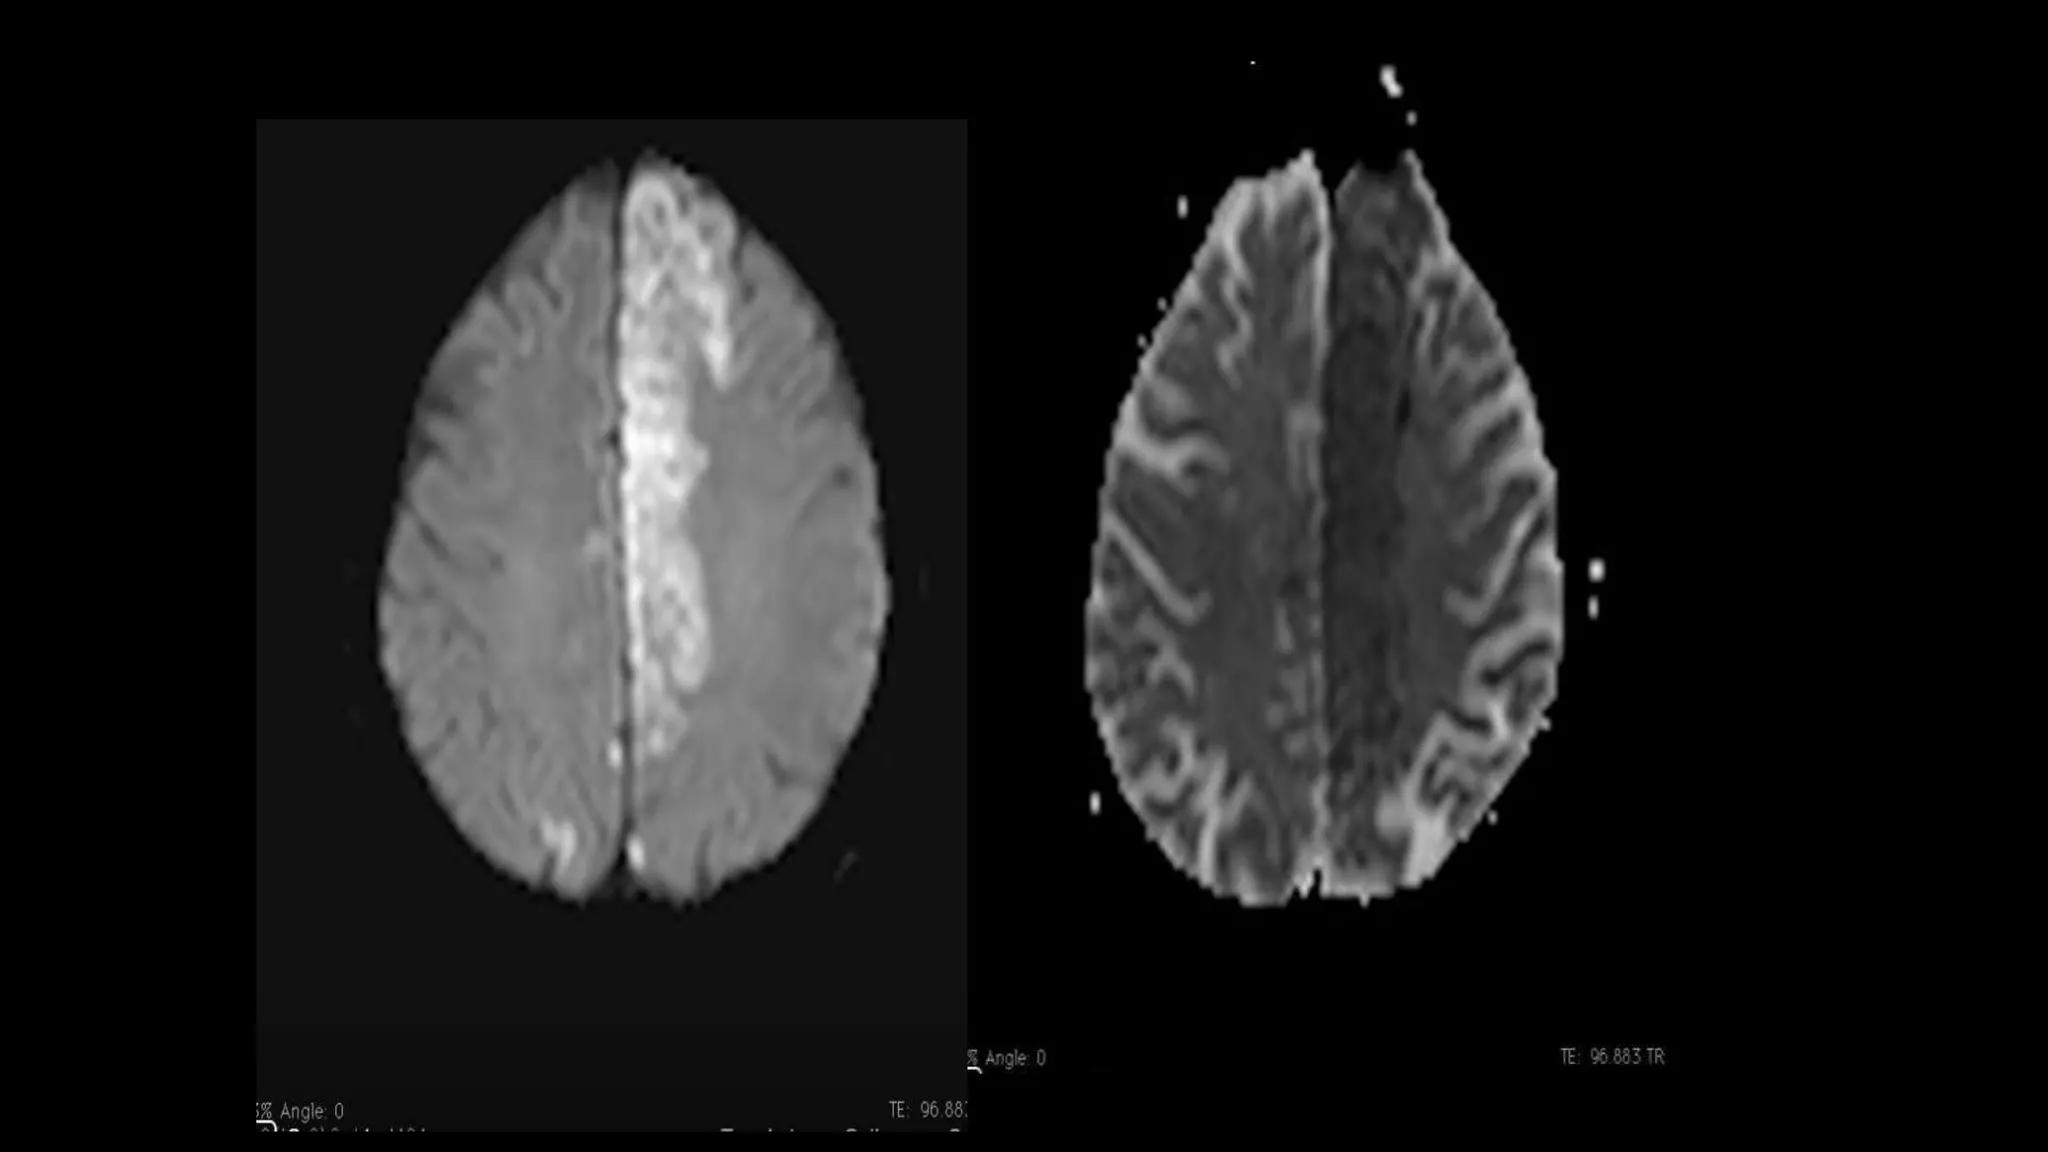

• #163 Another example showing circumferential intramural hematoma seen bilaterally causing expansion of the bilateral ICA . There is narrowed lumen of the right ICA and open lumen of the left ICA

• #164 Here is MR Angiography of cervical region showing narrowing & abnormal contour of the of the left vertebral artery causing cerebellar tonsilar infarction on left side.

• #165 Simultaneous small acute infarcts in multiple different vascular distribution…………..most commonly emboli is cardiac in origin Clinically silent , they convey risk of subsequent stroke

• #166 Diffusion wi shows multiple foci od hyperintensities in both the cerebral hemisphere and in multiple vascular territories..cortical , subcortical and deep regions are affected. Restriction is confirmed on ADC maps , indicating this represents acute infarcts. The distribution raises concern for central embolic source such as cardiac source.